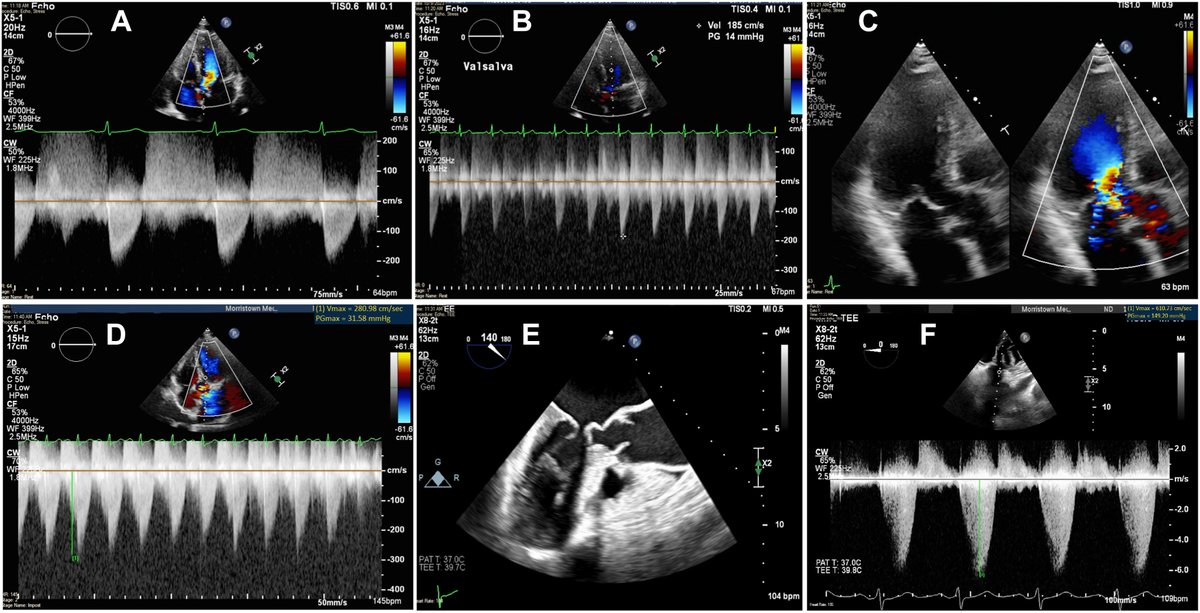

🔎 In symptomatic HCM, obstruction matters—but can be latent. Combining isoproterenol provocation with TEE may unmask LVOTO more sensitively than current approaches. Read more ⬇️ https://t.co/FjhZYaPYWm

#CJCO #OpenAccess